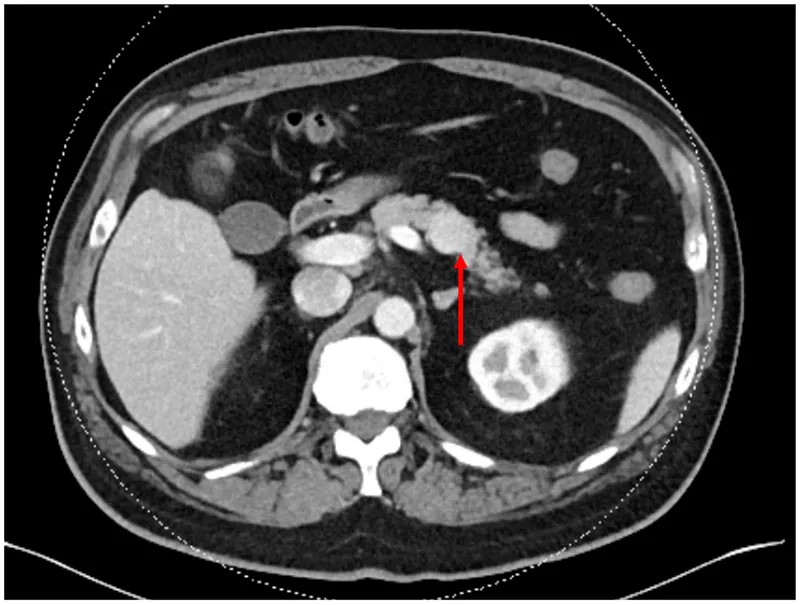

- Localization: Endoscopic ultrasound (EUS) is gold standard. CT/MRI.